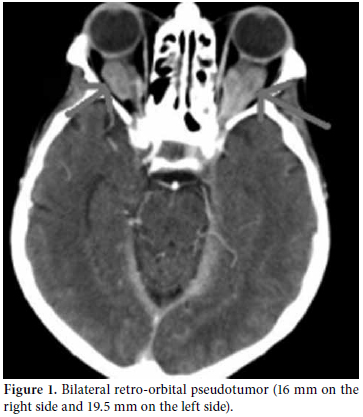

A 61-year-old male patient was admitted to our outpatient unit with dyspnea, edema on the legs, and chest pain. The physical examination was unremarkable except for exophthalmos, tachypnea, S3 edema, and bilateral pretibial pitting edema, and the laboratory investigation revealed the following levels: blood urea nitrogen 94 mg/dL, creatinin 1.38 mg/dL, and C-reactive protein (CRP) 1.53 mg/dl. The anti nuclear antibody (ANA) revealed a negative result. The globulin levels were within normal limits; therefore, IgG and E levels were not analyzed. The patient had no history of autoimmune or allergic diseases. An echocardiographic evaluation was performed to rule out heart failure and massive pericardial effusion, and a mass at the right atrial wall was detected. Nearly 1500 cc pericardial fluid was aspirated by pericardiosynthesis for the relief of the dyspnea. The examinations for tuberculosis revealed negative results, but atypical mesothelial and inflammatory cells were seen in the cytological evaluation. Therefore, computed tomography (CT) of the abdomen and thorax was ordered for further evaluation and pericardial effusion and periaortitis was detected beginning from the arcus and lasting to the abdominal aorta (Figures 1 and 2). On the cardiac CT scan, three soft tissues arising from the right coronary artery and extending to the right atrium were seen (Figure 3). The serologic tests for perinuclear anti-neutrophil cytoplasmic antibodies (p-ANCA) and cytoplasmic anti-neutrophil cytoplasmic autoantibody (c-ANCA) were negative. The radiological evaluation of the exophthalmos with cranial CT revealed bilateral retro-orbital pseudotumors, although the thyroidstimulating hormone level was normal (Figure 4). By all of these radiological findings, IgG4-related sclerosing vasculitis was first suspected, and the level of IgG4 was found to be 148 (0-125) U/ml. The patient was referred to the cardiovascular surgeons for a biopsy from the mass in the right atrium. The histological evaluation of the biopsy material revealed lymphoplasmacytic infiltration fibrosis, a lymphoid follicle, and eosinophilic infiltration. These findings were concordant with IgG4-related sclerosing vasculitis. The arterial constrictions in the right coronary artery and circumflex artery were removed by percutaneous balloon angioplasty and two cardiac stents a cardiac pacemaker were implanted.

The appropriate treatment was ordered as a pulse steroid of 1000 mg prednisolone and 500 mg cyclophosphamide every month in conjunction with oral immunosuppressive therapy. A radiological evaluation after three months revealed significant response and regression of the lesions. The mass in the right atrium had decreased to 16 mm, and the lesion on the retro-orbital area had decreased to 11 mm on the right and 12 mm on the left.